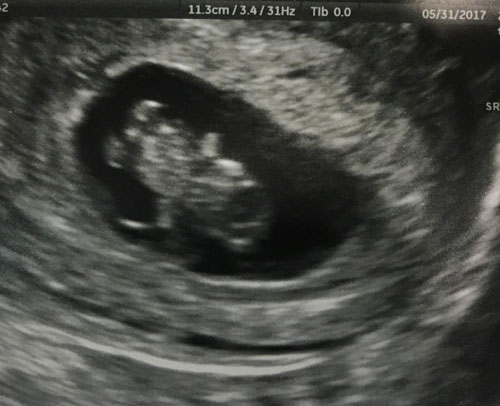

My husband and I are so happy to welcome our 3rd bundle of joy!